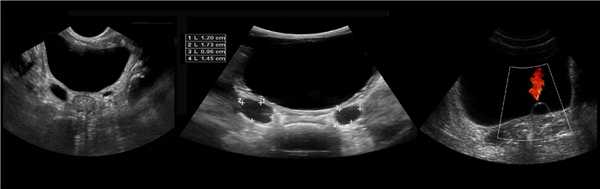

Рисунок. Двустороннее уретероцеле на УЗИ: в режиме ЦДК из верхушек уретероцеле определяется выброс мочи.